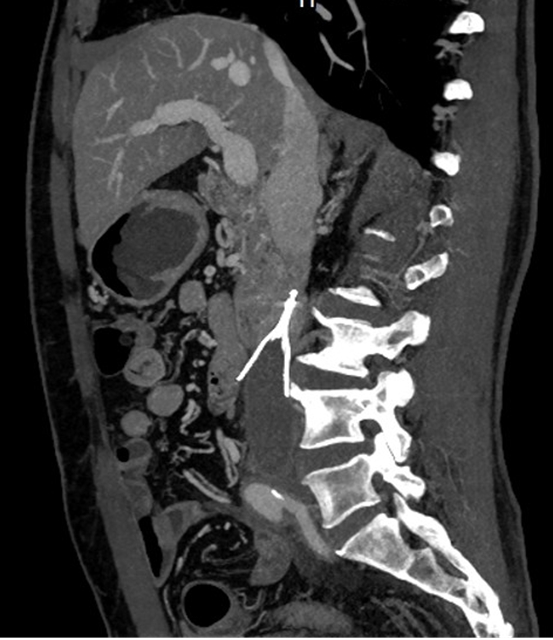

术前CT静脉血管成像,显示下腔静脉内滤器留置,滤器下方下腔静脉内血栓形成

入院后一系列全面且细致的检查结果令人揪心:下腔静脉滤器植入术后并发血栓形成:滤器以远的下腔静脉及双侧髂静脉内全程血栓形成,双下肢深静脉血栓形成(混合型,急性期)。

深入的病情分析清晰地指出,滤器植入长达 6 年,加之抗凝药物停用,致使下腔静脉及髂静脉血栓大量堆积,此刻单纯依靠抗凝治疗已难以有效化解危机,唯有彻底清除血栓才有可能降低远期并发症的发生风险。

结合老人过往病史以及各项检查数据来看,血栓处于急性期,而老人整体身体状况尚可,这为开展机械血栓清除手术创造了有利条件;但滤器植入时间远超滤器回收窗(通常滤器植入术后需要3月内取出),由此引发的滤器贴壁、辅支穿孔等棘手问题,让手术的难度和风险急剧攀升,一份严谨周密的手术预案成为手术成功与否的关键所在。